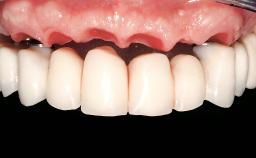

Conventional Loading of Two Implants in the Mandible and Final Restoration with a Bar-Supported RDP

A 63-year-old female patient was referred to the University Medical Center in Groningen, Netherlands, for dental implant treatment. The patient had been edentulous in the upper jaw for 20 years. The remaining teeth in the lower jar had been removed two years before the consultation. The patient was wearing her first maxillary denture and her second mandibular denture; the latter was 1 year old at the time. The conventional upper denture had functioned satisfactorily for many years, but the patient complained about reduced stability and insufficient retention of her lower conventional denture. Her medical history revealed no significant findings. The intraoral examination revealed minor resorption of the maxillary alveolar process and extreme resorption of the mandibular alveolar process.

Prosthesis Type RDP

Defining Characteristics Fully edentulous lower jaw to be rehabilitated with an implant-borne removable overdenture

Occlusal Scheme/Issues Balanced